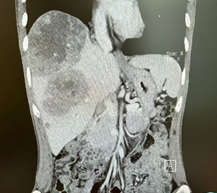

新辅助(两次HAIC和两个周期靶免治疗)后MR

由于病人一般情况较好,肝功能良好(Child-pugh A级),经多学科会诊临床确认肿瘤为IIb期肝细胞癌,属于可切除性肝癌,但存在高危复发因素,建议先行新辅助治疗后手术切除。经两次肝动脉关注化疗(HAIC)(奥沙利铂+5-Fu+亚叶酸钙方案)和两个周期的靶向免疫治疗(仑伐替尼+帕博利珠单抗方案),第二次介入造影是肿瘤血供不明显,第二次介入治疗4周后复查CT提示肿瘤缩小不明显但坏死征象明显,经MRI证实仍有少许血供,于是经多学科会诊后决定行前入路右半肝切除术。